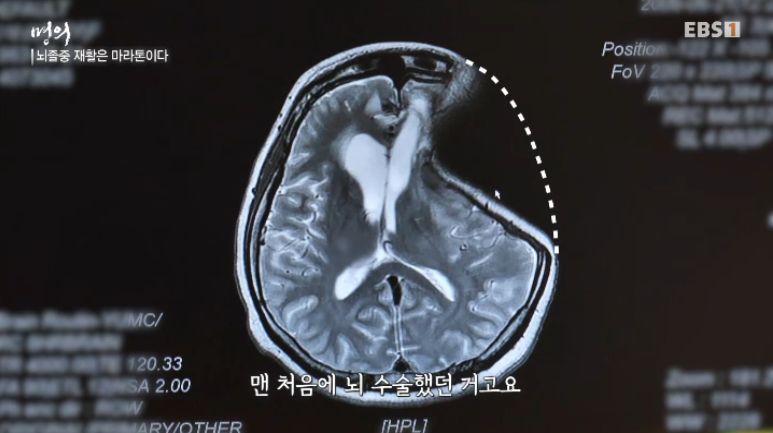

40대에 뇌혈관이 터져 생긴 뇌졸중. 응급수술까지 해야 했던 위급한 상황.

이번 환자는 1.5년이나 걸려 의식을 회복.

이후 몸에 달려 있던 있던 장치들을 하나씩 빼면서 회복, 움직일 수 있게 되면서 재활 치료 시작.

뇌출현 환자의 장기간 치료와 재활 후 어느 정도 회복된 뇌조직